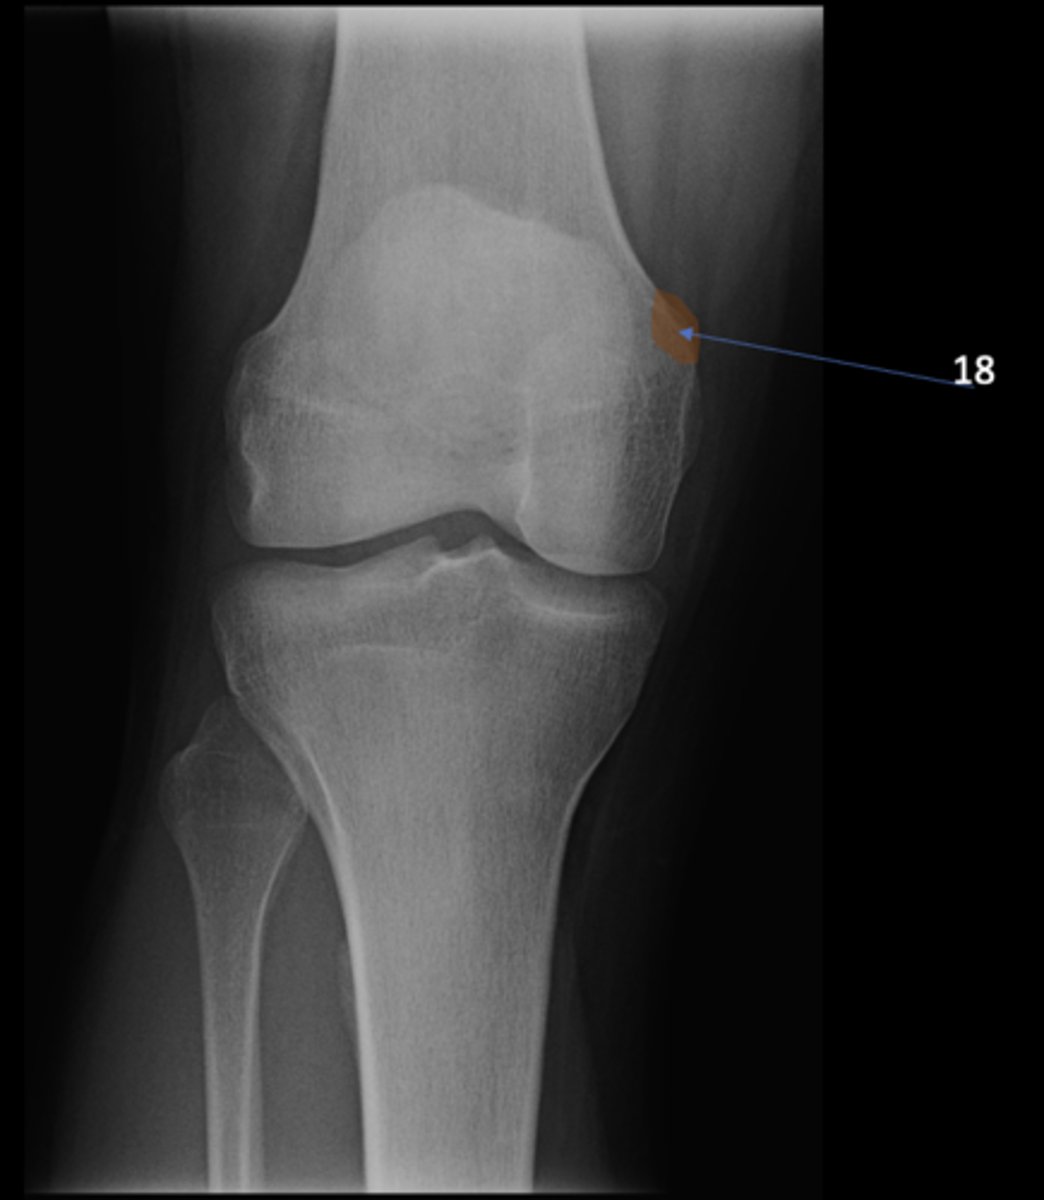

66

New cards

Adductor tubercle

ID 18

<p>ID 18</p>

67